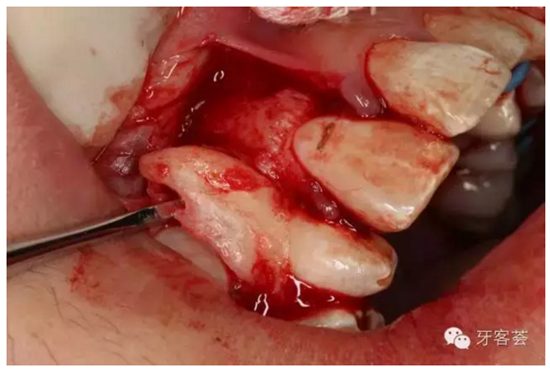

圖6:切開、翻瓣、暴露13牙冠。

圖7:12的牙根畸形肥大。正畸要求拔掉12.